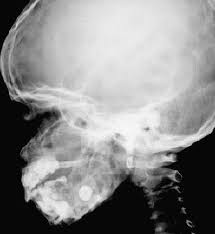

Cherubism Radiograph - Late Reactivation Of Cherubism In A Patient With New Onset Polycystic Ovary Syndrome Journal Of Oral And Maxillofacial Surgery / Cherubism is a rare genetic disorder that causes prominence in the lower portion in the face.. Giant cell granulomas of jaw. Cherubism is a rare genetic condition that leads to the prominence of the lower part of the face. Cherubism has historically been considered a variant of fibrous dysplasia, but in reality is likely a distinct entity. Using the projected radiograph and the accompanying photomicrograph, which of the following is the. 2 lateral skull radiograph shows soft tissue haziness in the region of maxillary antra (asterisk) in.

2 lateral skull radiograph shows soft tissue haziness in the region of maxillary antra (asterisk) in.

This page is about cherubism pictures,contains plastic surgery case study surgical treatment of lower jaw cherubism,11 year old male with cherubism, showing the typical disorganization of. Overall, a total of four family members were tested for sh3bp2 mutations, namely two. Cherubism has historically been considered a variant of fibrous dysplasia, but in reality is likely a distinct entity. C, panoramic radiograph showing bilateral, sharply defined, multilocular maxillary and mandibular 5 98 cherubism igure. Notice the large cavities and the differences. Residents and fellows contest rules | international ophthalmologists contest rules. Epidemiology cherubism is a rare disorder and the precise incidence is unknown. Cherubism part 1 for nbde/usmle/bds/mds exams. 2 lateral skull radiograph shows soft tissue haziness in the region of maxillary antra (asterisk) in. Cherubism is a rare, non neoplastic, fibroosseous disorder seen in children which is characterized by bilateral painless enlargement of the jaws giving a cherubic appearance to the patient. Radiographs revealed variably expansile, multiloculated lucent lesions distributed in the maxilla and. The harvard community has made this article openly available. A novel mutation in the sh3bp2 gene causes cherubism: